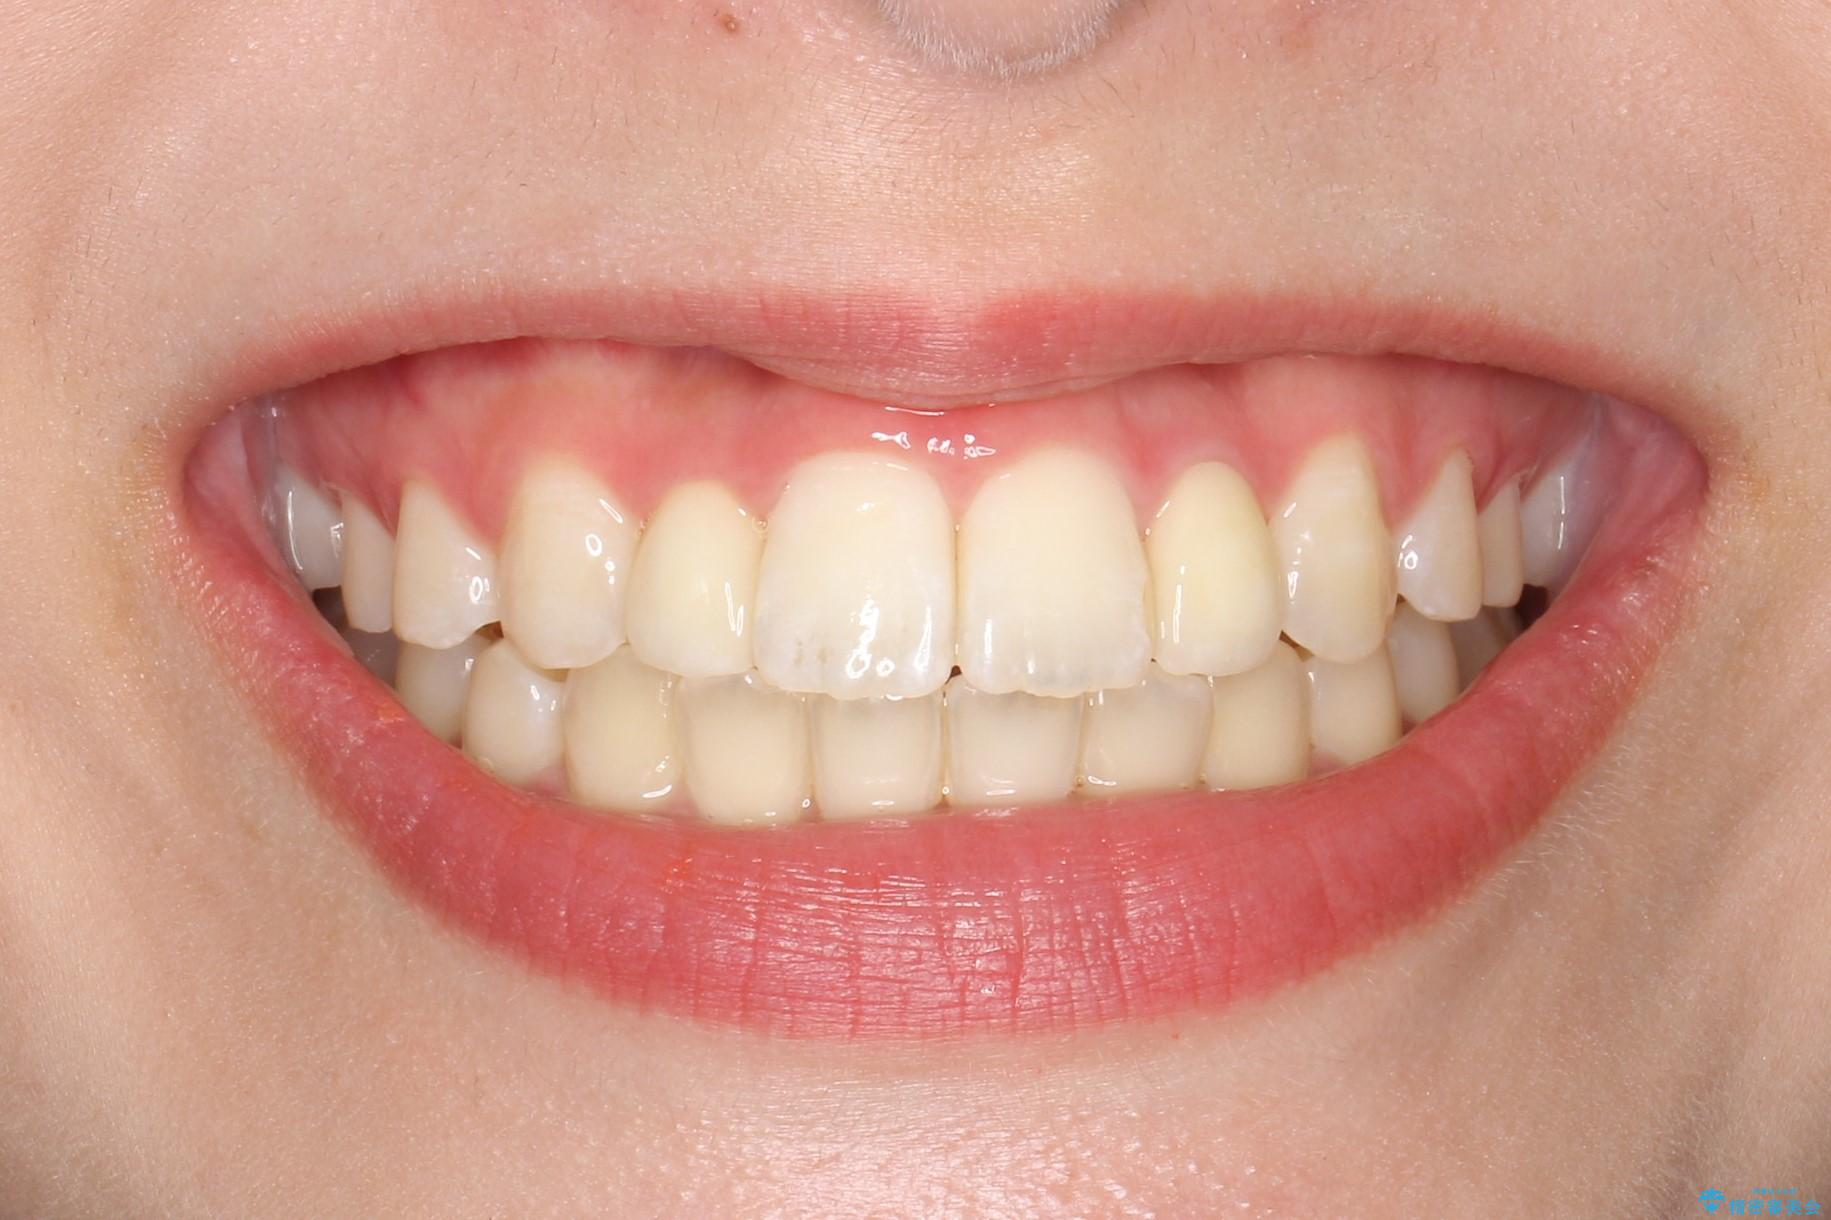

歯の形態修正も含めた矯正治療&セラミック治療

時間はかかりましたが、きれいな笑顔になりました。

かぶせ物の種類:PFZ standard